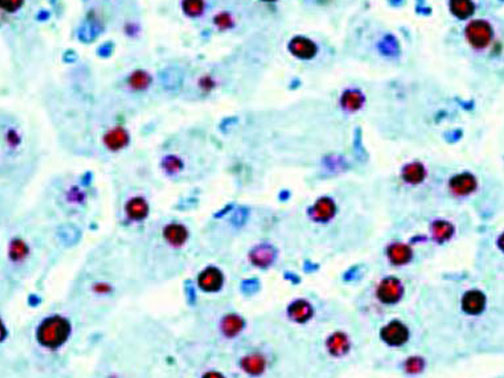

It is the ICU physician who is most likely to witness one of the deadliest manifestations of the abnormal immunological response, the cytokine storm syndrome (CSS). This response is also referred to by some as the cytokine release syndrome (CRS). CSS is characterized by continuous activation and expansion of macrophage and lymphocyte populations, which secrete large amounts of cytokines, causing the cytokine storm. This massive cytokine release is akin to hemophagocytic lymphohistiocytosis (HLH) disease, a syndrome characterized by initial unchecked and persistent activation of cytotoxic T lymphocytes and NK cells.

Clinical and laboratory manifestations of HLH include fever, enlarged liver and/or spleen, neurologic dysfunction, coagulopathy, liver dysfunction, cytopenias (i.e., low levels of erythrocytes, leukocytes, and/or platelets), hypertriglyceridemia, hyperferritinemia, hemophagocytosis, and eventually diminished NK cell activity as the immune system becomes progressively paralyzed. HLH can be familial (primary HLH) or secondary to another disease process (sHLH), such as rheumatic disease, in which it is referred to as macrophage activation syndrome (MAS, characterized by elevated ferritin).